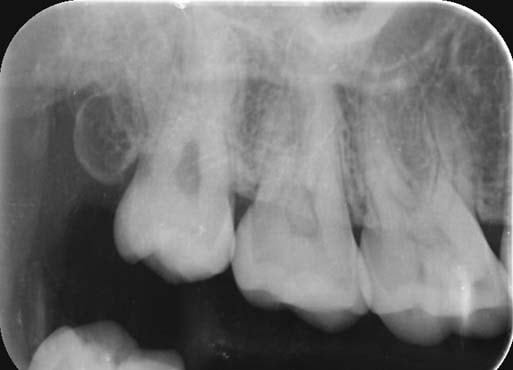

Gyökérfelszívódás

A gyökérfelszívódás a foggyökér megrövidülését jelenti. Tejfogazatban ez egy kívánatos reakció, mely a növekvő maradófog miatt jön létre. A maradófog hatására a tejfogak gyökere elkezd felszívódni, a tejfog meglazul, majd végül kiesik és helyét átveszi a megfelelő maradófog. Sajnos ez a folyamat maradófogazatban is megfigyelhető. Oka lehet fogakat ért baleset, trauma, súlyos fertőzés, de fogszabályozó kezeléseknél is előfordul. Ennek megfelelően a gyökérfelszívódások csoportosítása: belső - gyulladásos eredetű (pl.: fogbélgyulladás miatt), felületi (fogszabályozás során) és helyettesítő (balesetet szenvedett fogaknál).

Fogszabályozás során felületi, gyulladásmentes gyökérfelszívódás alakulhat ki. Fontos tisztában lenni azzal a ténnyel, hogy gyökérfelszívódás minden fogszabályozó kezelés során fellép, csupán oly kis mértékű, hogy nem lehet diagnosztizálni! A fogmozgatás miatt a foggyökerek csúcsa lekerekedik, majd a kezelés végén spontán helyreáll.

Ritkán, súlyos esetben a foggyökér jelentős megrövidülése jön létre. Ennek mértéke megjósolhatatlan, akár a fog meglazulásához, elvesztéséhez is vezethet. Legtöbbször 1-1 fogat érint, a generalizált, teljes fogazatot érintő gyökérfelszívódás extrém ritka.

Kialakulásának pontos oka még nem ismert, több faktor együttes jelenléte szükséges, és valószínűleg genetikai háttere is van. Hajlamosító tényező lehet a korábban balesetet szenvedett fog, vagy ha a kezelés során túl nagy erőkkel mozgatjuk a fogakat. Az önligírozó fogszabályzók helyes használatával ennek lehetősége minimalizálható.